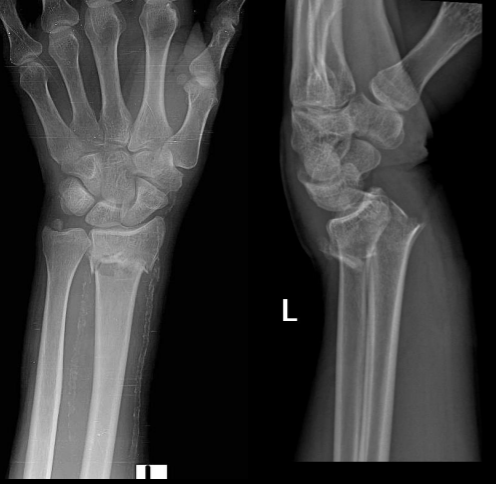

Características Fx colles

A

Mano extendida

Desviación dorsal epifisis

Asociada a osteoporosis >40 años

Características Fx smith

Fx en flexion

Desviación palmar epifisis

Colles

Smith